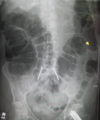

Sigmoid volvulus

Sigmoid volvulus ## Footnote dilation causes the classic coffee-bean sign, a pathognomonic of sigmoid volvulus.